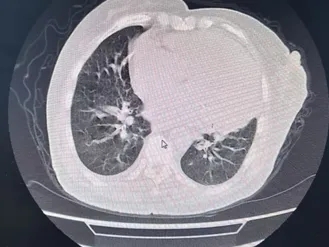

胸部CT:考虑双肺轻度肺间质水肿。肺动脉增粗,心脏增大,冠脉钙化,少量心包积液,双侧胸膜腔积液,提示心衰征象。肺气肿;双肺慢性细支气管炎。右肺中叶、左肺上叶条状肺不张伴炎症。胸壁皮下轻度水肿。